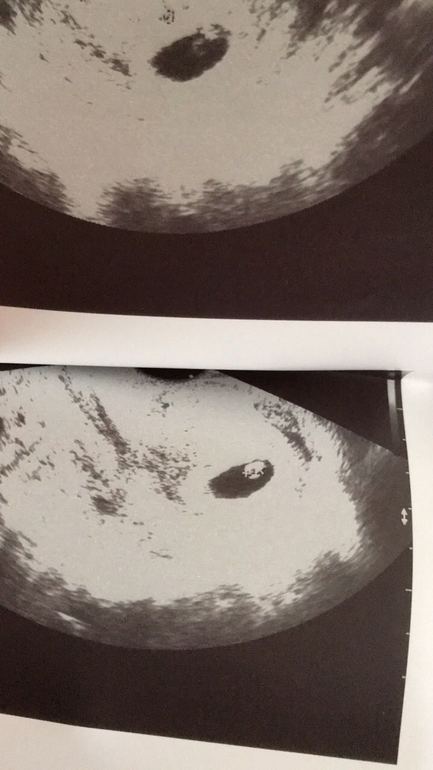

Естественно потом началась тестомания, ХГЧ..мы ярчали, росли. Чуть погодя я пошла к своему гинекологу, все подтвердилось. Мы становились еще счастливей..Первые удары сердечка, последующие узи..все это казалось огромной сказкой.

В один из дней, не попав к своему гинекологу на узи, (тянуло немного живот), я записалась к другому врачу. Это был какой-то ад. Сорок минут меня ковырял датчиком узист с каменным,серым лицом. Заключение: беременность 9-10 недель, двойня, фето-фетальный синдром.. Рекомендации: Узи экспертного класса. Естественно шок, ибо до этого никаких подозрений ни на что похожее не было. Естественно повторное УЗИ.. которое ничего не показало. Сказали "прекрасный плод, предположительно мальчик, сердечко бьется - 169 ударов в минуту, рожать будем в сентябре." Меня отпустило. Довольная, как лань, я выпорхнула из кабинета в коридор, где меня ждал обеспокоенный муж. Своей счастливой улыбкой и словами, что у нас очень-очень предположительно мальчик и все в норме, я развеяла и его страхи тоже...

Шло время, я записалась на первый скрининг.. На сроке 11 недель и 3 дня я посетила врача. Когда поднесли датчик к животу, я сразу поняла, что что-то не так. Животик моего малыша была размером больше чем его голова... 30 минут длилось узи, все было как в тумане.. Широкое ТВП, диагноз предположительно мегацистис.. И тут началось, узи, узи4D, узи экспертного класса, меня осматривали доктора и кандидаты медицинских наук.. Все твердили в один голос "Аборт".

На сроке почти 14 недель, в день аборта, на последнем узи было видно, что животик ребенка надулся мочой уже настолько, что сдавил сердечко... 13 марта все закончилось.